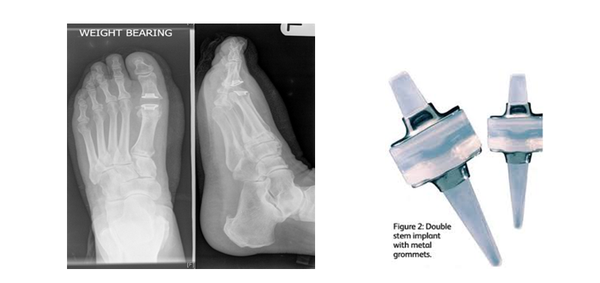

Joint implant

This operation is recommended for those with moderate to severe degenerative joint disease. The silicone joint implant has a likely life span of 10-15 years. They have been used widely in the UK and US over the past 20 years. The procedure involves making an incision along the top of the big toe joint, removing both sides of the joint and placing a silicone hinged joint in the remaining space. They are not indicated in patients who have an active lifestyle or the under the age of 65 years.